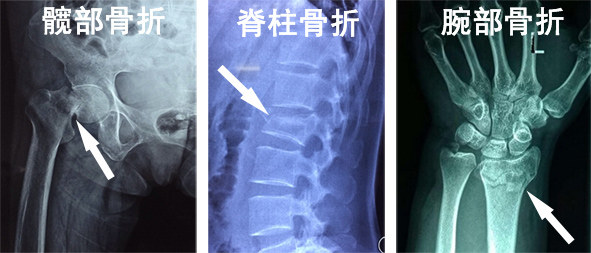

北京医院骨科副主任医师申剑向39深呼吸介绍,老人摔倒后最常出现的骨折包括脊柱骨折、髋部骨折和手腕骨折,其中髋部骨折最为凶险,因为这种骨折患者活动受限,需要卧床休养,除了疼痛,还容易出现下肢静脉血栓、心衰、肺炎、褥疮等一系列并发症,随时会被夺去生命,有“人生最后一次骨折”之称。

老人摔倒后常见的三种骨折。/ 资料图片